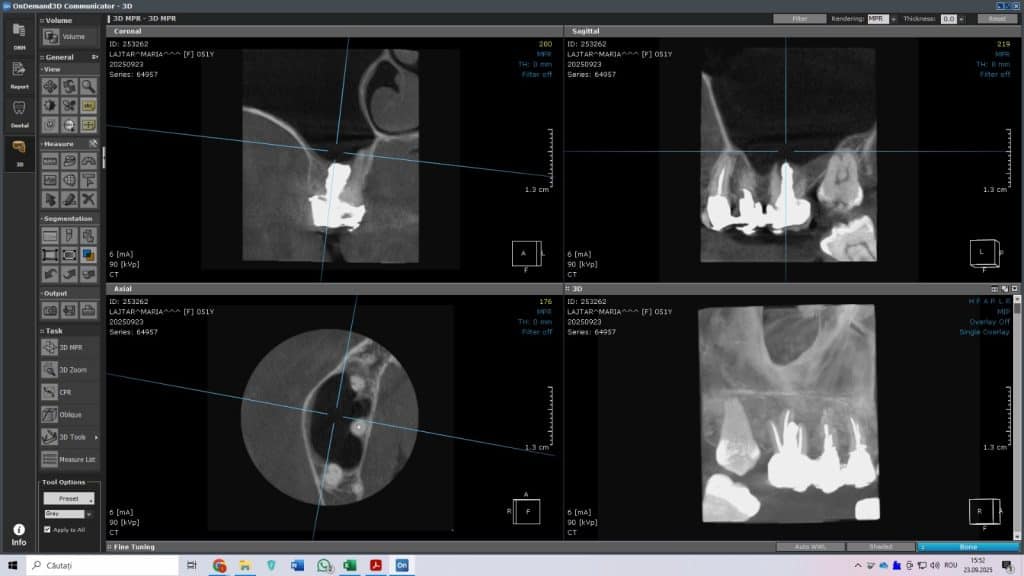

Fig. 1- Imagine CBCT înainte de tratament – perforația și sinusul infectat

În cazul prezentat:

• dintele avea o perforație mare la bază,

• exista legătură directă cu sinusul maxilar infectat,

• metodele clasice nu puteau fi folosite în siguranță.